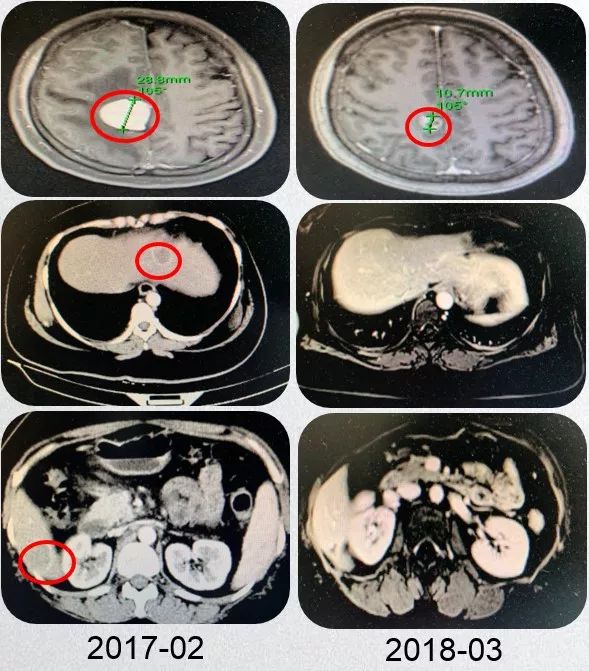

2017年2月,患者自述经常性头痛,间断钝痛,头晕伴有双眼模糊。颅脑MRI示(图2):右顶叶及小脑半球占位,结合患者病史符合脑转移瘤可能性大。

PFS1为14个月。

图2 患者颅脑转移瘤可能性大

结合患者病史、穿刺病理结果,再次重申乳腺癌HER2阳性患者靶向抗HER2治疗的重要意义,最终患者及家属表示同意。二线给予紫杉醇+卡培他滨联合曲妥珠单抗(TXH)方案治疗8周期,具体剂量为:紫杉醇 175mg/m2 静滴d1, 卡培他滨 1000mg/m2 口服bid d1-d14,曲妥珠单抗初始8mg/Kg,后续6 mg/Kg静滴d1,期间给予唑来膦酸预防骨不良事件和给予降低颅内压、保肝等对症治疗。治疗完成后给予全脑放疗DT50Gy/25f。8周期化疗及放疗完成后,综合疗效(图3)评价为部分缓解(Partial Response,PR)。

图3 患者TXH方案8周期治疗和放疗后复查